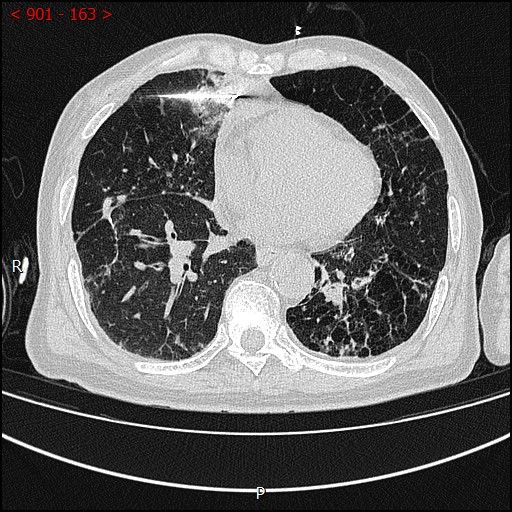

术前影像

男性患者,68岁,检查发现右肺中叶肿块,大小约3.5cm×2.4cm,因患者有慢性支气管炎、肺气肿、肺大泡,基础病较多,无法耐受常规外科手术治疗;经与患者本人及家属多次沟通。血管介入科团队根据患者具体情况决定对该患者施行CT引导下肺肿瘤射频消融术。经全科术前讨论:肿瘤位置毗邻心脏、纵膈、胸膜多处重要器官,手术要求穿刺精准,消融位置精确,尽量避免恶性心率失常,心脏包膜、胸膜、纵膈损伤。经过前期的精心术前准备,2023年7月18日,在血管介入科团队和CT室默契配合下,此次射频消融手术顺利完成。手术全过程仅用时约40分钟,其中消融时间约5分钟。CT观察下见肿瘤形变,周围肺组织呈现“晕”征,提示本次消融范围基本覆盖全肿瘤。术中患者无疼痛并且未产生并发症。本次手术达到杀死肿瘤细胞的同时,最大限度的减少创伤、保留肺组织。